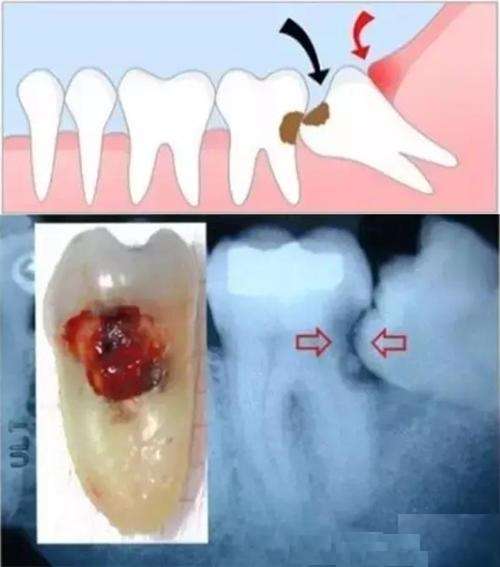

横生智齿

横着的智齿,一直不疼,需要拔吗

横生的智齿一定要拔除吗?